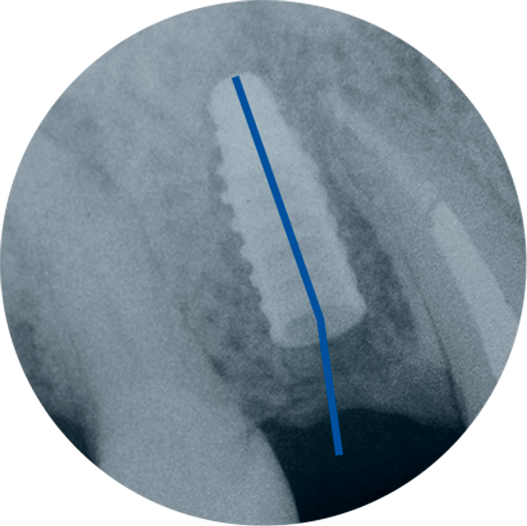

Veja os resultados do Implante e Prótese na posição ideal:

Implante instalado.

Observe a divergência entre os eixos cirúrgico e protético.

Componente protético customizado.

Observe o refinamento do eixo protético possibilitado pela tecnologia do Sistema Arcsys.

Autor: Prof. Dr. Rafael Cury Cecato